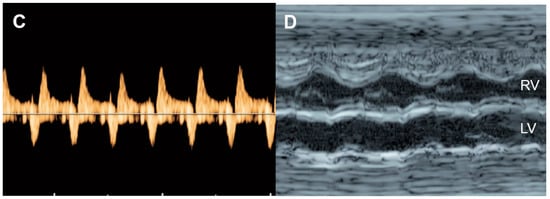

| Venous Doppler (umbilical vein: UV & ductus venosus: DV | Normal Doppler UV ![]() DV ![]() | Reversed ductus venosus flow UV ![]() DV ![]() | Pulsatile flow in the umbilical vein UV ![]() |

| Arterial Doppler (umbilical artery) | Normal Doppler![]() | Absent end-diastolic flow![]() | Reversed end-diastolic flow![]() |